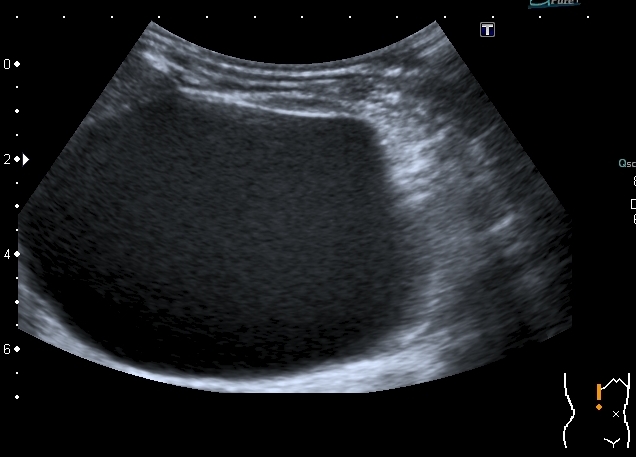

Тему уже давно закрыли, но вот свежая "красивая" картинка; левая почка незначительно увеличена в размерах, без изменений ЧЛС, со слов больного он уже несколько лет наблюдается у уролога: